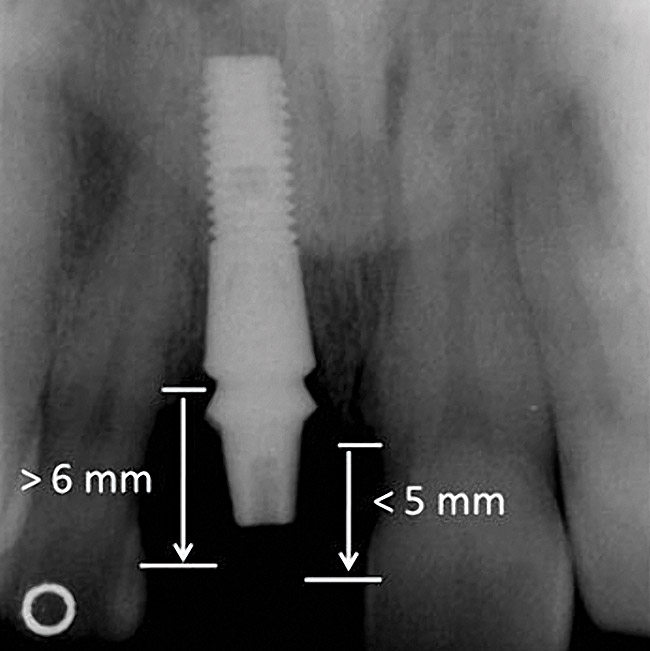

Figure 4  Characterization of the interproximal bone and tooth contacts: A periapical radiograph assists in measuring the distance from bone crest to the adjacent tooth contact points for missing tooth No. 8. The mesial bone crest to the adjacent tooth contact distance is < 5 mm, while the distal bone crest to adjacent tooth contact distance is > 6 mm (Fig 4). One-year following implant placement, conservation of these dimensions is revealed (Fig 5). The clinical photograph (Fig 6) of the lateral incisor adjacent to tooth No. 8 implant crown demonstrates that the absence of distal interproximal (papilla) fill related to the observed bone crest to contact distance exceeds 6 mm.

Figure 5  Characterization of the interproximal bone and tooth contacts: A periapical radiograph assists in measuring the distance from bone crest to the adjacent tooth contact points for missing tooth No. 8. The mesial bone crest to the adjacent tooth contact distance is < 5 mm, while the distal bone crest to adjacent tooth contact distance is > 6 mm (Fig 4). One-year following implant placement, conservation of these dimensions is revealed (Fig 5). The clinical photograph (Fig 6) of the lateral incisor adjacent to tooth No. 8 implant crown demonstrates that the absence of distal interproximal (papilla) fill related to the observed bone crest to contact distance exceeds 6 mm.

Figure 6  Characterization of the interproximal bone and tooth contacts: A periapical radiograph assists in measuring the distance from bone crest to the adjacent tooth contact points for missing tooth No. 8. The mesial bone crest to the adjacent tooth contact distance is < 5 mm, while the distal bone crest to adjacent tooth contact distance is > 6 mm (Fig 4). One-year following implant placement, conservation of these dimensions is revealed (Fig 5). The clinical photograph (Fig 6) of the lateral incisor adjacent to tooth No. 8 implant crown demonstrates that the absence of distal interproximal (papilla) fill related to the observed bone crest to contact distance exceeds 6 mm.

Additional attention must be paid to the osseous architecture related to the adjacent teeth, as this controls interproximal tissue form.7 The crest of healthy bone is 4.5 mm to 5 mm from the contact point between anterior teeth8; a similar 5-mm distance from the contact point to the bone crest has been measured between an implant and natural tooth. An important and additional rule to guide esthetic implant outcomes is that the adjacent tooth should possess interproximal bone levels no further than 6 mm from the natural tooth contact point (Figure 4 through Figure 6). While the ideal distance is justifiably indicated to be 5 mm, this 6-mm rule establishes a point at which marked interproximal tissue deficiencies and asymmetry will not be overcome.